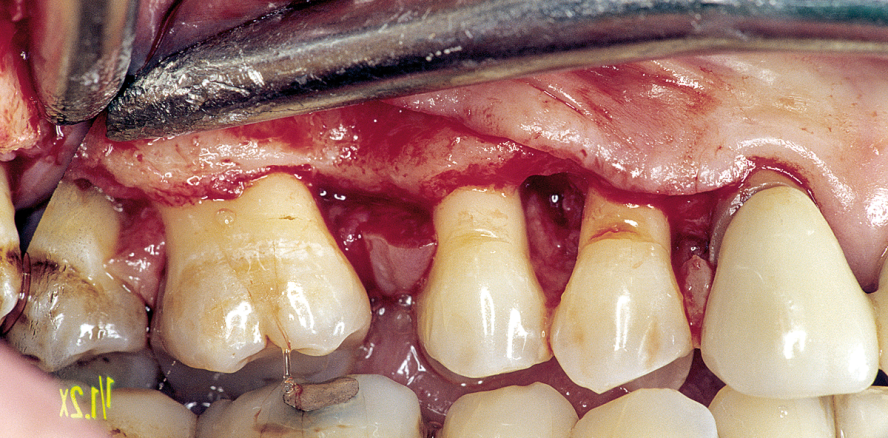

a) Anatomie: Behandelte fortgeschrittene Parodontalerkrankungen sind klinisch stabil, zeigen aber in den im plantatrelevanten anatomischen Knochenabschnitten (bukkale Lamellen, interapproximales Septum) weitere Abbauvorgänge durch Entzündung (Abb. 1 und 2).1

Daraus resultiert ein zweizeitiges Vorgehen mit (i) Entfernung prognostisch unsicherer Zähne, (ii) parodontaler Zieltherapie zur Sicherung des Restzahnbestandes, ergänzt durch (iii) mikrochirurgische Revision tiefer Resttaschen vor Implantation zum weiteren Entzündungsschutz (Abb. 3 und 4). Die Implantatplanung bleibt vorläufig. Ein definitiver Kostenvoranschlag wird erst nach funktioneller Entlastung und digitaler Beurteilung der Implantatknochenanatomie erstellt.